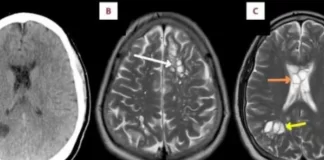

Ankohej nga dhimbja e kokës së vazhdueshme, mjekët i gjejnë vezë...

Një burrë në Florida që vuante nga migrena e vazhdueshme iu tha se kishte vezë krimbi në trurin e tij.Pacienti 52-vjeçar kërkoi ndihmë mjekësore...